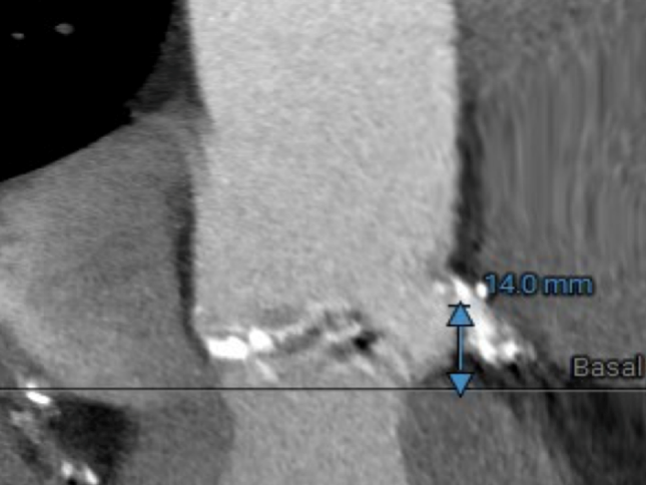

LEFT CORONARY

左冠开口高度14.0mm